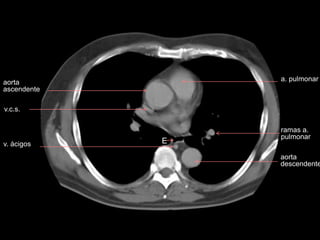

TOMOGRAFIA

v.c.s.

carina

v. ácigos

aorta

ascendente

a. pulmonar

izquierda

descendente

br. derecho

receso

pleuro-

acigoesofágico

rama a.

pulmonar

tronco a.

pumonar

a. pulm. der.

br. izquierdo